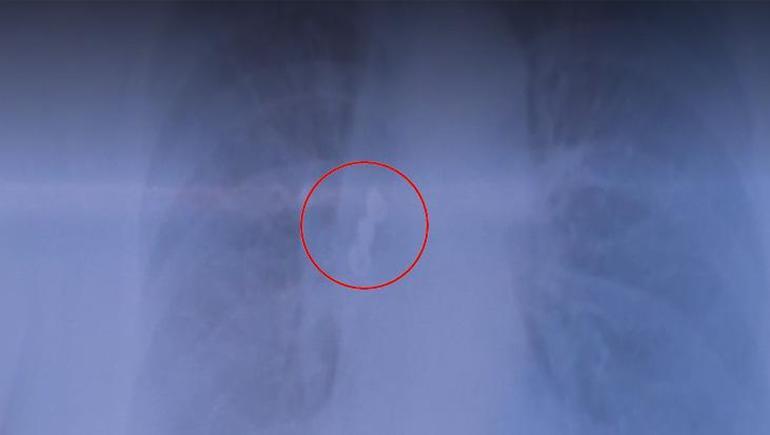

Kadın hastanın üst arka tarafta bulunan üçlü kaplama dişi akciğerine kaçtı. Sabah uyandığında dişlerinin yerinde olmadığını gören hasta acilen hastaneye başvurdu. Çekilen röntgen filminde dişlerin akciğerde olduğu görüldü. Hasta şanslıydı, çünkü soluk borusu tamamen tıkanabilirdi. Akciğerdeki diş bronkoskopi yöntemiyle çıkarıldı.

Göğüs Hastalıkları Uzmanı Prof. Dr. Levent Alpay, akciğer filminde üç dişten oluşan kaplama köprüsünün aspire edildiğini fark ettiklerini ve hastayı hemen yatırdıklarını söyledi. Sabah uyandığında dişlerinin yerinde olmadığını gören hastanın, dişleri yutmuş olabileceğini düşündüğünü belirten Alpay, bu tür durumlarda genellikle mideye kaçma ihtimalinin daha yüksek olduğunu vurguladı.

“Çekilen akciğer filminde kaplama dişin üç dişten oluşan kısmının aspire edildiğini görerek hastamızı hemen yatırdık. Sabah uyandığında dişlerinin ağzında olmadığını gören hasta, “Acaba yuttum mu?” diye düşündü. Genelde bu tür durumlarda yutma söz konusu olur.

Oldukça nadir rastlanan bir durumdur. Bu tür vakaları genelde çocukluk çağında görürüz; erişkinlerde ise nadir görülür. Nefes borusunu tıkayabilir, hastanın hayatını tehdit edecek ciddi problemler oluşturabilir. Bu nedenle hastalara acil müdahale gerekir.”